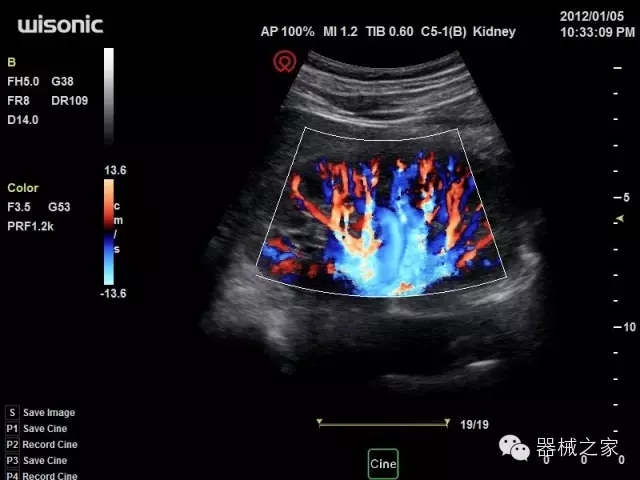

臨床圖片賞析

產(chǎn)品特點(diǎn)

·智能微血流成像技術(shù):智能微血流捕捉技術(shù)可以提取出隱藏在背景噪聲中的弱血流信號(hào),大大提高低速血流的敏感性;

·移植S40高端臺(tái)式彩超高端平臺(tái)技術(shù),滿足超聲科腹部、淺表、婦產(chǎn)科、心血管、肌骨等應(yīng)用,提供超聲科完美解決方案;